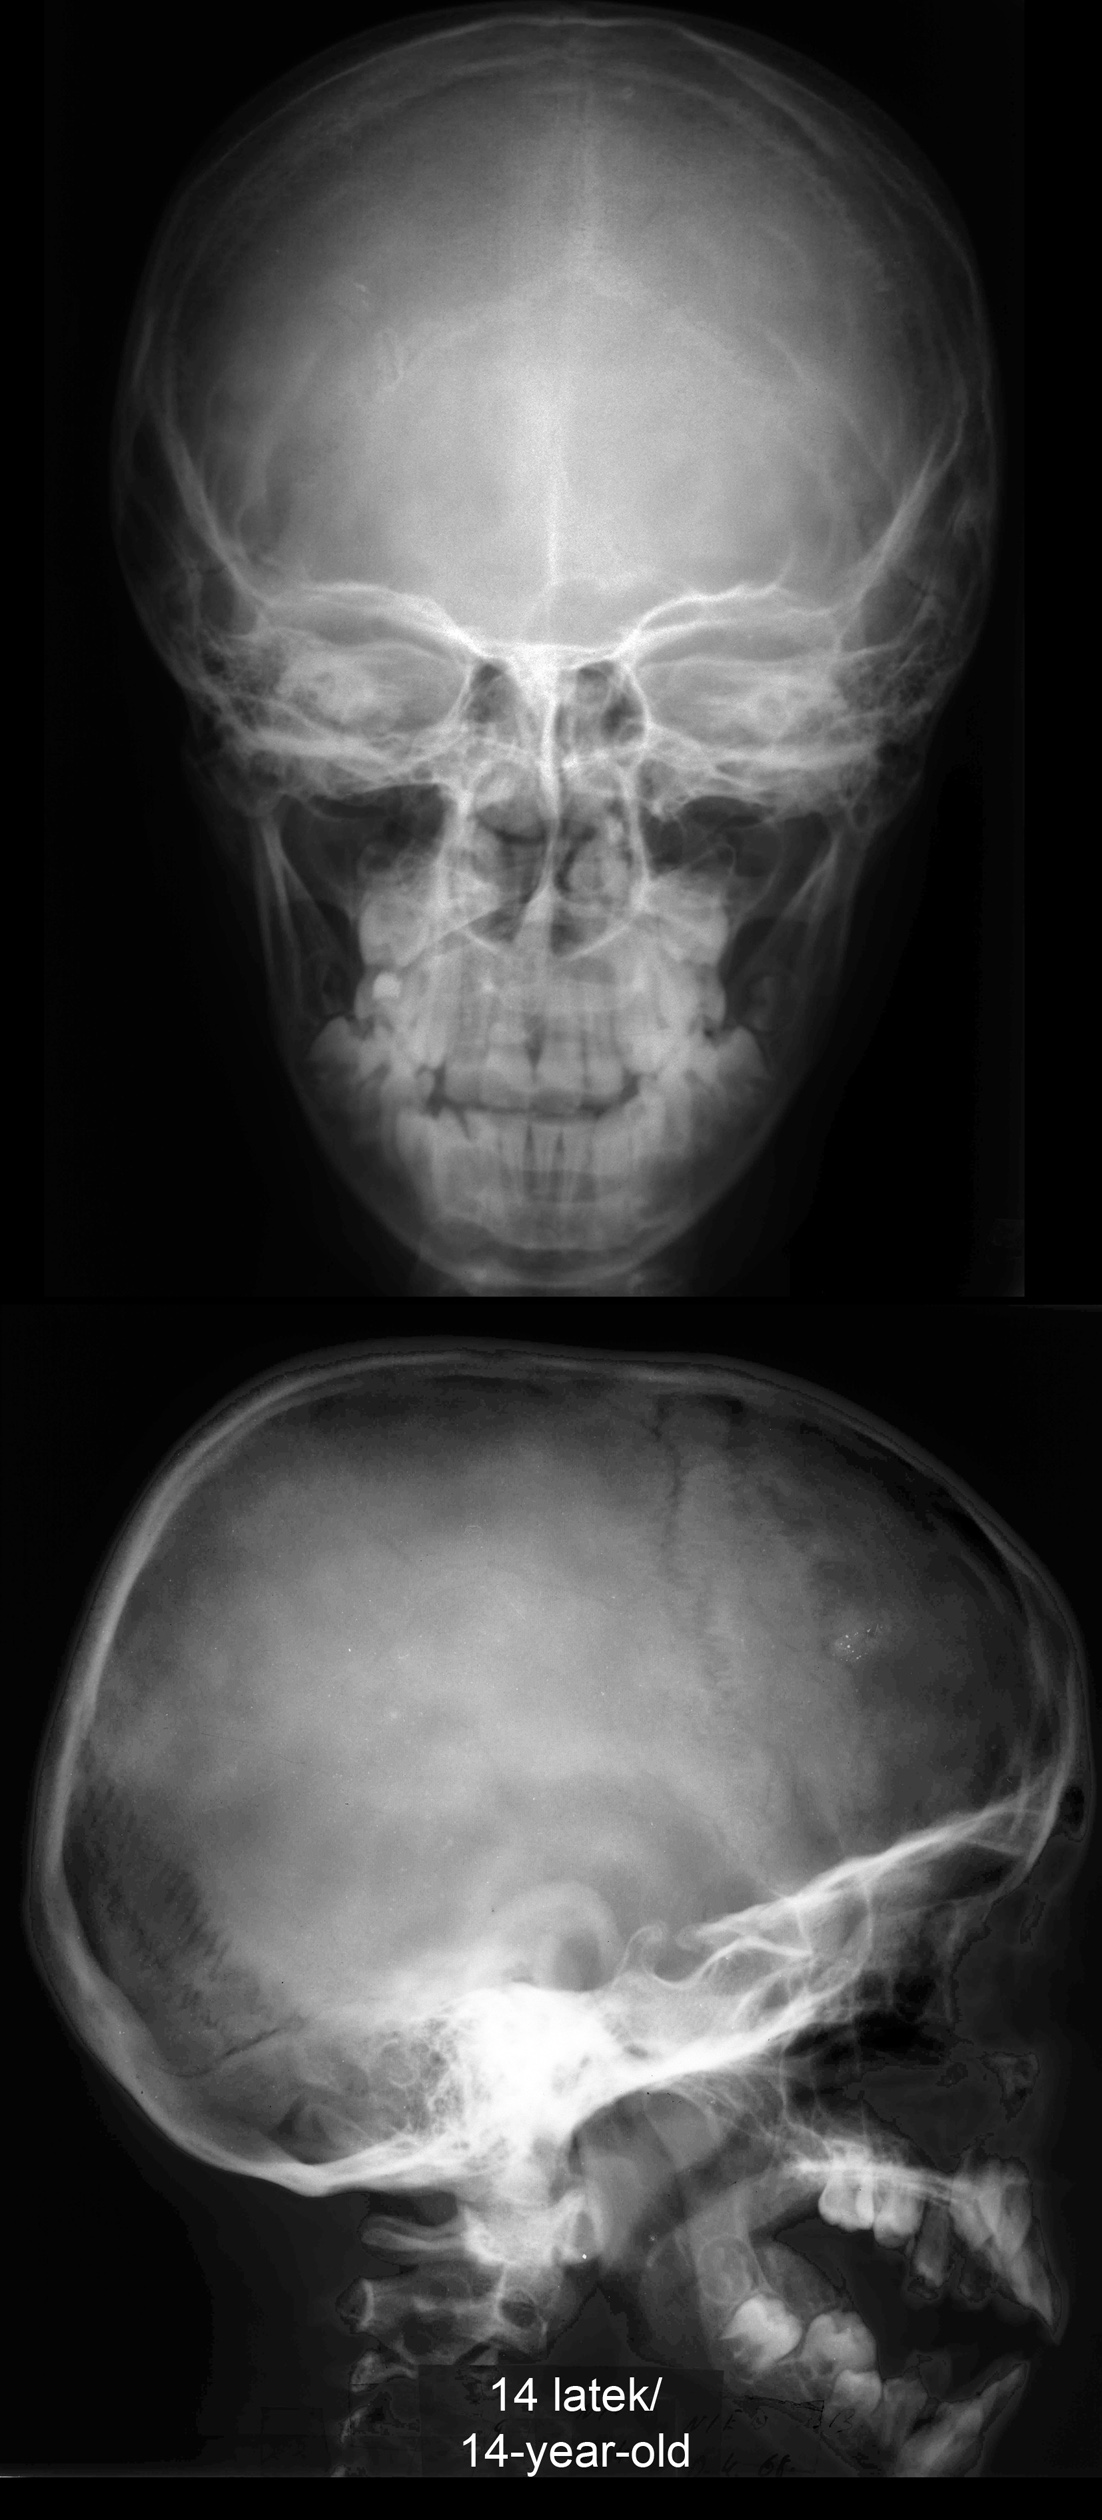

RTG głowy 14-latka.

RTG głowy 25-latka.

RTG głowy 70-latka.

. RTG głowy 14-, 25- i 70-latka.